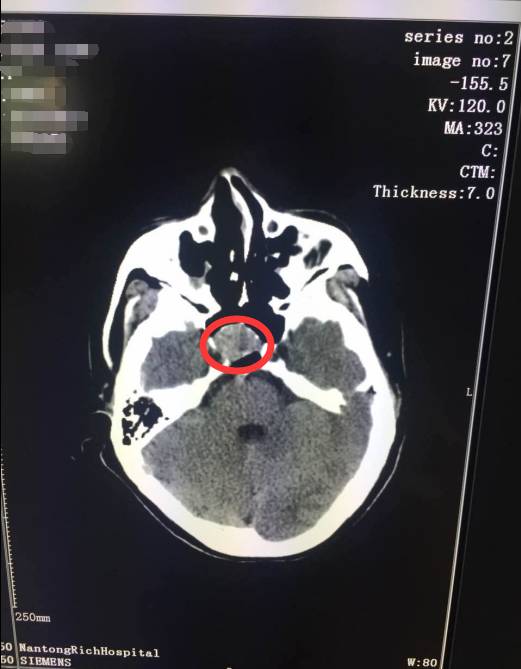

据瑞慈医院神经外科主治医师钱志坤介绍,于女士的垂体瘤是大型垂体瘤,直径超过了1厘米,形态很不规则,肿瘤偏向右侧,侵犯右侧海绵窦,包绕右侧颈内动脉,处理不当的话,极有可能造成颈内动脉、动眼神经等重要的血管、神经损伤,加重病情甚至出现生命危险。

图为:红圈位置即为垂体瘤